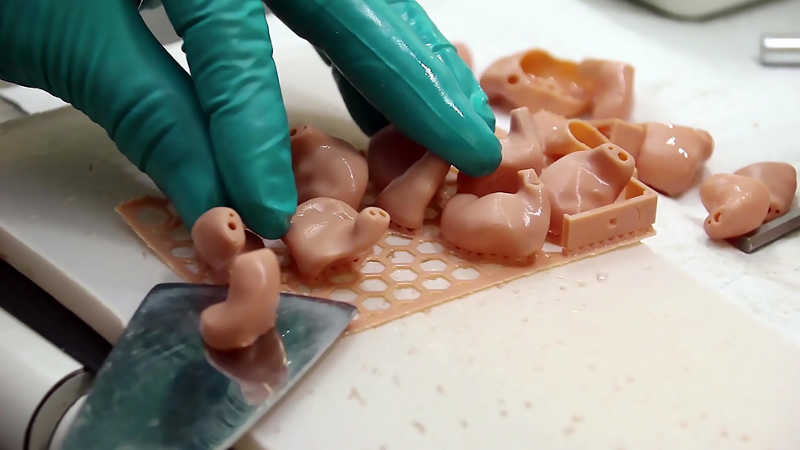

Ricoh seems to have found a promising niche in the 3D print world: anatomical models.

Materialise Mimics inPrint Certification Program Clears Ultimaker and Formlabs for Medical 3D Printing

Materialise’s announcement today of FDA-cleared medical model 3D printing encompasses vat polymerization and material extrusion technologies in addition to PolyJet.

FDA-Cleared Medical 3D Printing with Stratasys and Materialise

3D printing medical models offers benefits to patients and those providing their care with highly accurate patient-specific anatomies able to be held, examined, and practiced on.